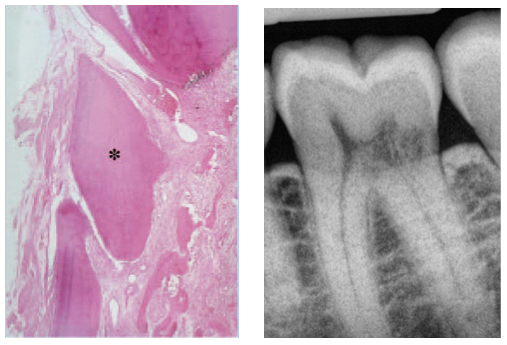

H & E staining reveals the resorption tissue as a highly vascular granulation tissue containing mononuclear and multinuclear clastic cells, and resorption lacunae (See Figure 11). Typically there are no acute or chronic inflammatory cells present, unless periodontal microorganisms secondarily infect the area. It is common to find an intact predentin/dentin layer protecting the pulp, however this layer may be breached in very large Class IV lesions, resulting in pulpal perforation.

Figure 11- Arrows point to mononuclear and multinuclear clastic cells and resorption lacunae. The asterisk labels an intact layer of predentin/dentin protecting the pulp.